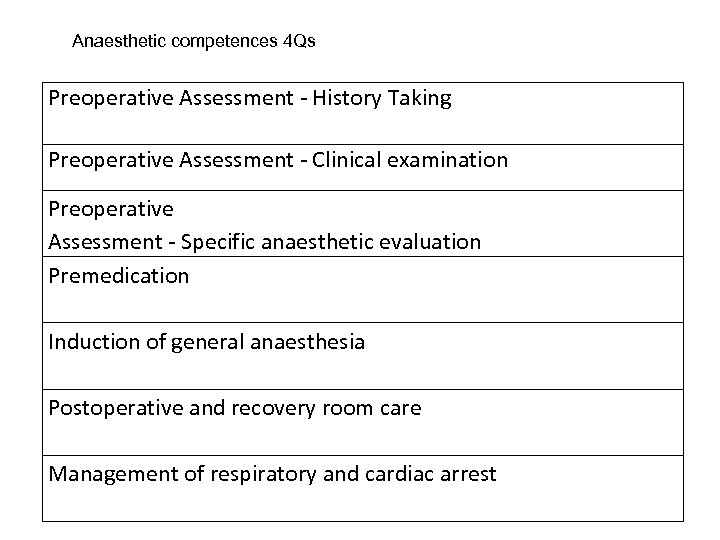

Anaesthetic competences 4 Qs Preoperative Assessment - History Taking Preoperative Assessment - Clinical examination Preoperative Assessment - Specific anaesthetic evaluation Premedication Induction of general anaesthesia Postoperative and recovery room care Management of respiratory and cardiac arrest